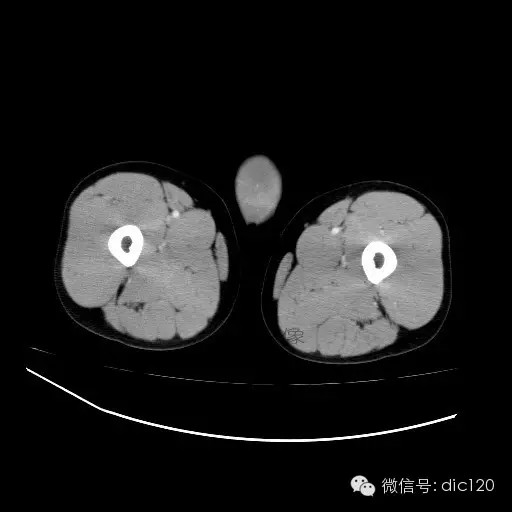

【影像表现】

青年男性,右侧睾丸肿大,边界清晰,增强后睾丸不均匀中度强化,内可见多灶囊变坏死区,动脉期肿块内有细小动脉血管显示,延迟期可见分隔样强化,鞘膜囊可见积液。

定位定性:右侧睾丸恶性肿瘤。

【影像诊断】

右侧睾丸精原细胞瘤,右侧睾丸鞘膜积液。